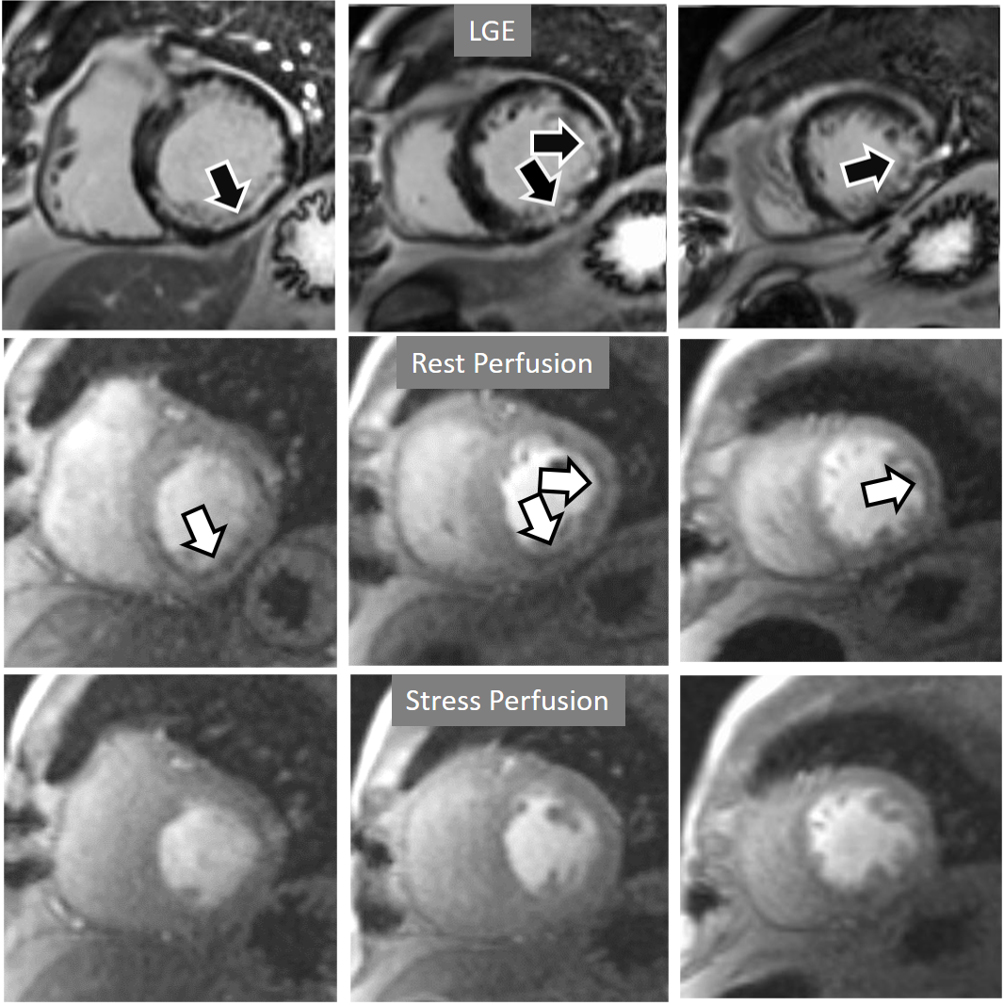

The presence of inducible residual peri-infarction ischemia in a territory with a previous MI has been addressed by the consideration of the extension of a stress perfusion defect in comparison with that of the LGE. Those defects with equal size on both sequences would be labelled as “fixed” (Fig. 16), while those perfusion defects exceeding the area of MI would be considered as “partially reversible” (Fig. 17), independently of rest perfusion studies. The diagnostic performance of the latter finding for the diagnosis of a residual significant stenosis in the infarct-related artery has been found to be adequate, though a good deal of cases with apparently fixed defects had also significantly obstructed arteries [46].

Fig. 16.Stress/Rest perfusion in chronic myocardial infarction. Perfusion defect during stress (performed in first place) (black arrow), not present at rest, matching the area of LGE (white arrow) in a case of large anterior subendocardial MI.

Fig. 17.Stress/Rest perfusion in chronic myocardial infarction. Perfusion defect during stress (performed in first place) (white arrow), not present at rest, fairly larger than the region of LGE (black arrow) in a patient with a subendocardial inferior MI.